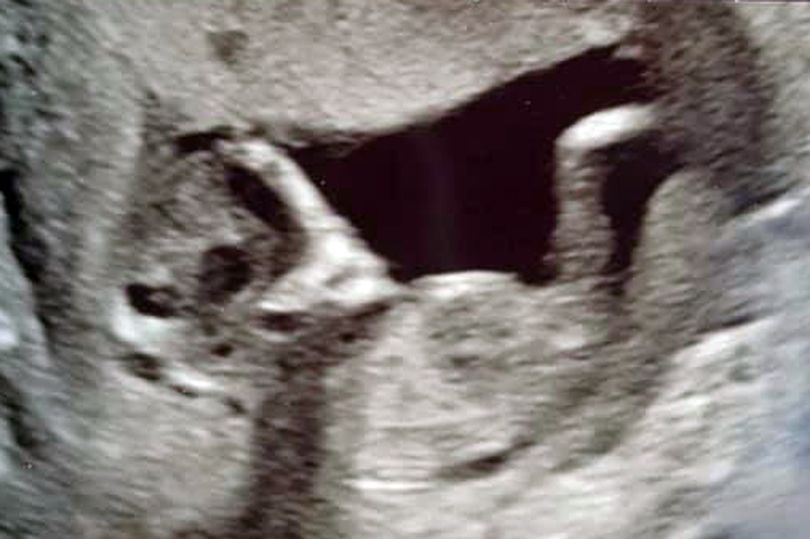

O tânără a rămas însărcinată la numai 16 ani și, firește, a mers la medic pentru a face o ecografie. Până aici, absolut nimic anormal. Dar adolescentei nu i-a venit să creadă ce a putut vedea pe imaginea respectivă.

Sophie Scott, în vârstă de 16 ani, a tras o sperietură teribilă în momentul în care a văzut pe ecran ceva cu totul neașteptat. Era „chipul unul extraterestru”, a spus ea, menționând că acel chip ciudat apărea chiar lângă bebelușul ei. Totodată, fata a explicat că nici chiar medicii nu au putut ajunge la o concluzie după ce au văzut imaginea.

„Am mai văzut un chip lângă bebelușul nostru, iar forma capului era exact ca cea a unui extraterestru. Am fost un pic speriați, dar apoi ne-am amuzat de situație. Cu toate acestea, nimeni nu și-a putut da seama despre ce a fost vorba, de fapt”, a spus tânăra mamă.

Copilul adolescentei ar urma să vină pe lume în luna octombrie a acestui an.